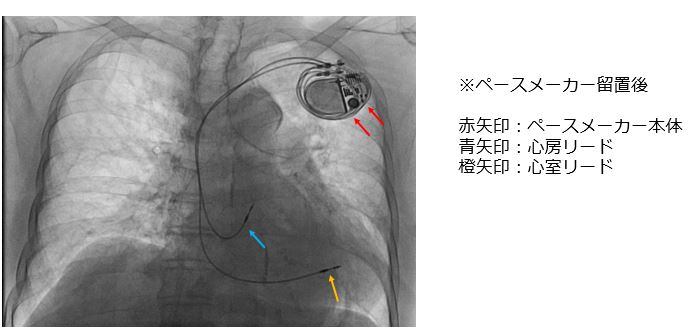

症状が出る場合には、心臓に植え込むことで、電気を直接心臓に送るペースメーカーを植え込みます。